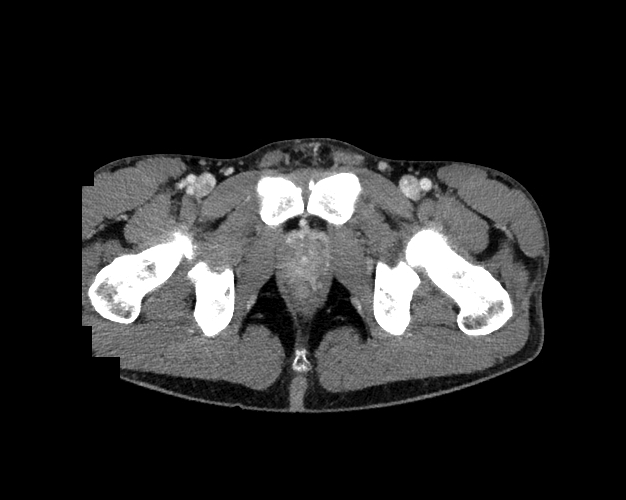

Pelvis

Covers pelvic MRI anatomy.